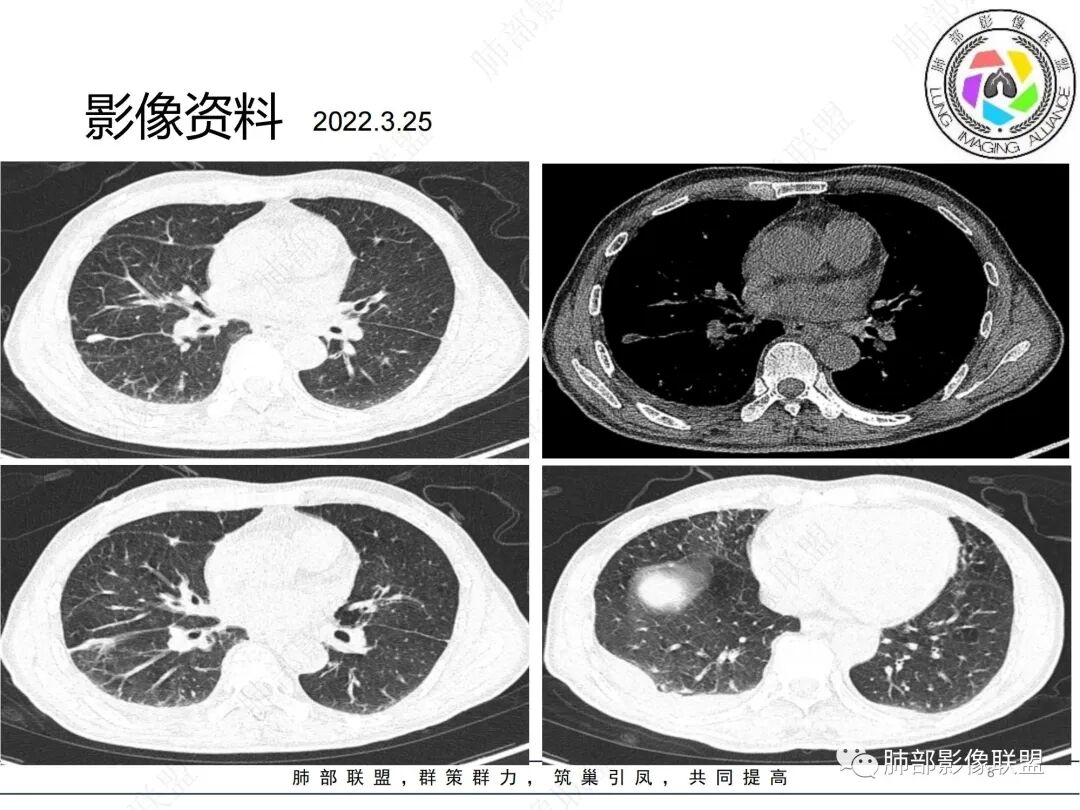

2、影像特点:双肺多发结节及条索影,边缘清晰,右肺上叶可见网格影,右侧胸腔少量积液;颈部、纵膈及腹部多发淋巴结肿大,大部淋巴结强化不均,呈环形强化,内部见低密度坏死区,部分淋巴结坏死不明显,尤其是腹部淋巴结密度较均匀。